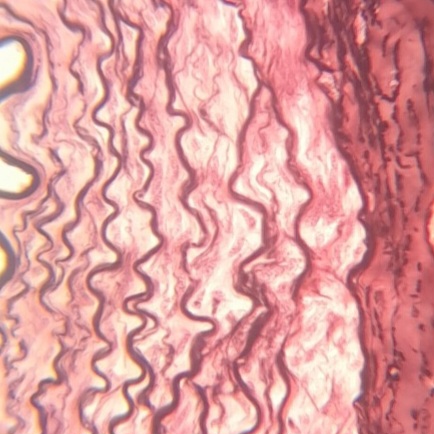

Sistema Tegumentar

O sistema tegumentar, o maior órgão do corpo humano, composto por: pele, pelos, unhas e glândulas associadas, desempenhando funções essenciais de proteção, regulação e percepção sensorial. A pele é formada por três camadas principais: a epiderme, que é a camada externa composta por epitélio, queratina e melanócitos, a derme, que contém tecido conjuntivo, vasos sanguíneos, nervos, folículos pilosos e glândulas, e a hipoderme, a camada mais profunda, composta por tecido adiposo. O sistema tegumentar regula a temperatura corporal, protege contra patógenos, e é um importante órgão sensorial, permitindo a detecção de toque, dor, temperatura e pressão.